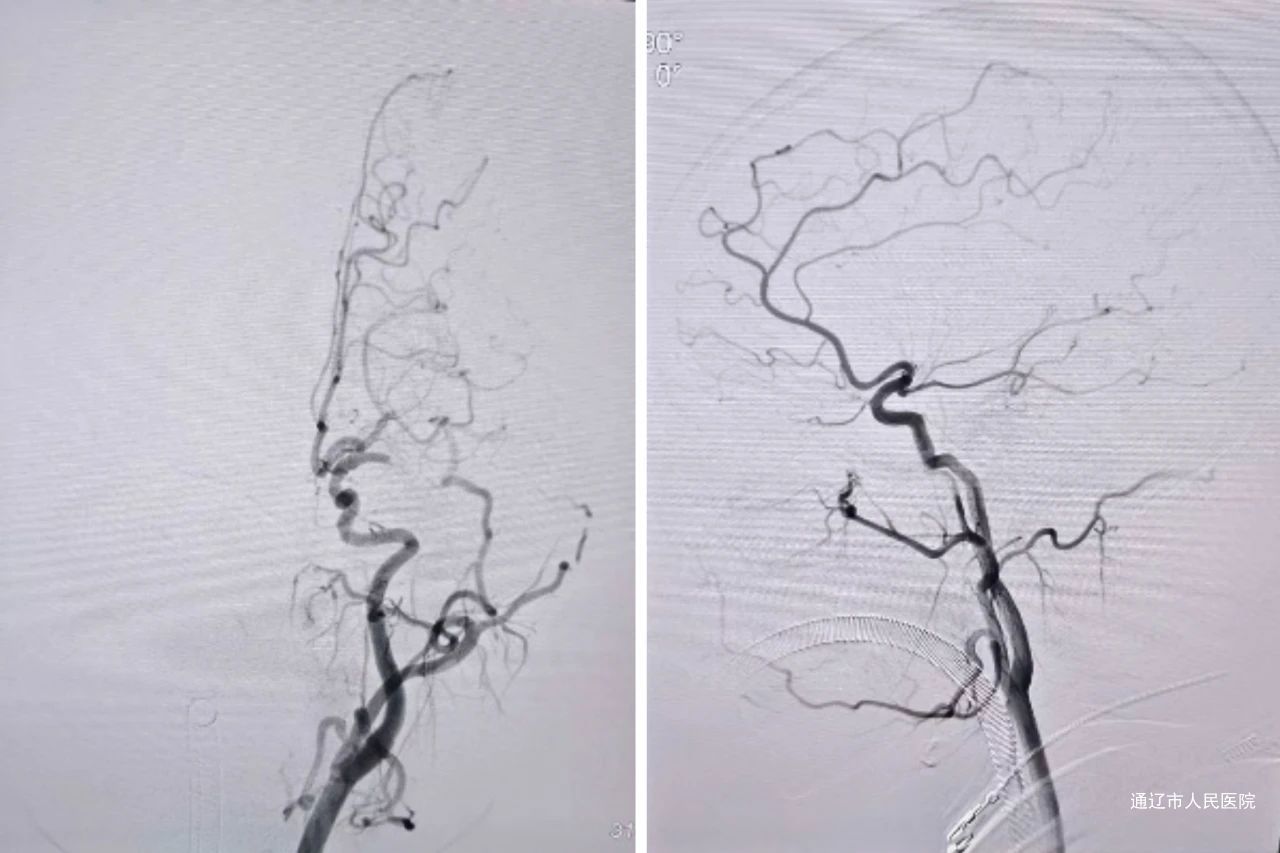

神经内四科团队立即开展评估,紧急启动血管内治疗。脑血管造影显示患者左侧大脑中动脉M1段闭塞,随即采用支架取栓联合抽吸术进行治疗。手术过程顺利,一次性实现血管再通,并成功取出3条长度约2.7cm的质韧白色血栓。术后病理检查显示,血栓成分为纤维蛋白样及红细胞聚合物。术后患者症状完全缓解,神经系统评分由术前10分恢复至0分,达到理想治疗效果。

(术前可见左侧大脑中动脉闭塞)

(术后左侧大脑中动脉再通)